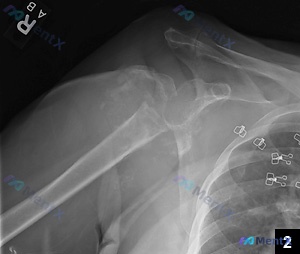

整理了一个有点意思、甚至有点“矛盾”的骨科病例,先把基础信息放出来: 基础情况:62岁女性,因持续性肩部疼痛求医。 关键矛盾点:她明确报告没有近期或过去的外伤史、感染史。 影像初步结果:右肩部X光提示—— - 肱骨近端复杂性骨折:累及解剖颈及大结节,伴有明显移位和多发骨折碎片 - 盂肱关节脱位:肱骨...